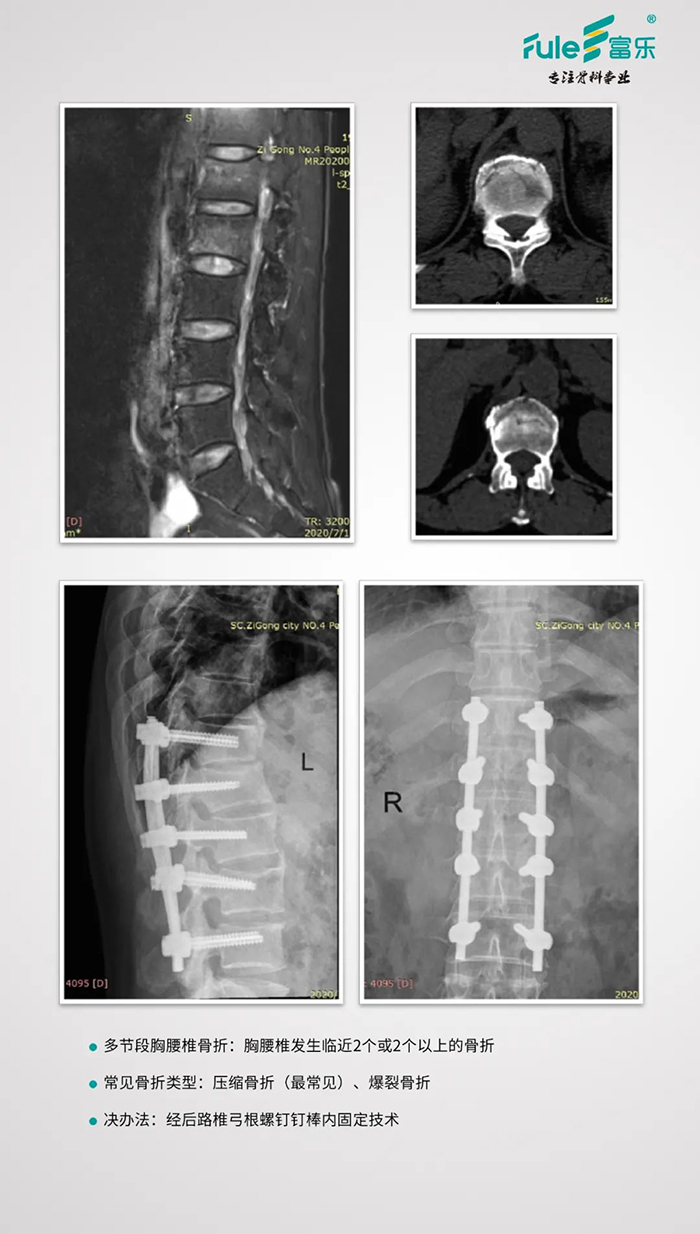

皮外导板辅助经皮椎弓根螺钉置入治疗多节段胸腰椎骨折

临床应用

■术前——钉道的测量与模拟置钉

![]()

■术后——复查X片、CT,评估手术效果